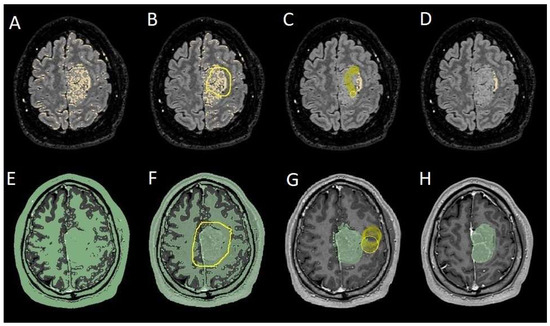

The patients underwent magnetic resonance imaging (MRI) at our center using a 1.5T or 3T Tesla MRI machine (Ingenia 3T, Philips Medical Systems, Best, The Netherlands) with the standard oncological protocol [14]. Specifically for analysis, the sequences collected were T1-weighted with contrast enhancement to estimate tumor volume and conformation and FLAIR (fluid-attenuated inversion recovery) to quantify PE (Figure 1). We manage the preoperative imaging in a DICOM (digital imaging and communications in medicine) format. The images from the T1-weighted sequences with contrast enhancement and FLAIR sequences in the DICOM format were processed through the Slicer website [15]. Tumor and PE segmentation was performed using a voxel-based analysis that integrated automated and manual methods (Figure 2).

Figure 1. Sequences selected for the segmentation. (AC) Coronal, sagittal, and axial FLAIR sequences to quantify PE. (DF) Coronal, sagittal, and axial T1-weighted sequences with contrast enhancement to estimate meningioma volume. FLAIR: fluid-attenuated inversion recovery; PE: peritumoral edema.